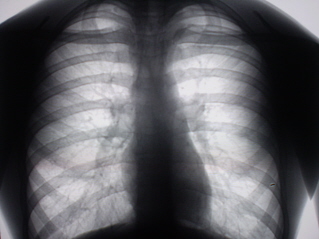

Цифровое стандартное флюорографическое профилактическое исследование (проведено на цифровом флюорографе «Ренекс – Флюоро»). На цифровых флюорограммах, произведенных в прямой, правой и левой боковых проекциях с обеих сторон определяется синдром двусторонней аденопатии. С обеих сторон определяется резкое увеличение и гомгенизация тени корней за счет резко гиперплазированных, в основном, бронхопульмональных лимфатических узлов с довольно чёткими, ровными контурами. Структура тени однородная. На фоне гиперплазированных лимфатических узлов чётко дифференцируются просветы главных бронхов.

Иллюстрации 1, 2, 3.